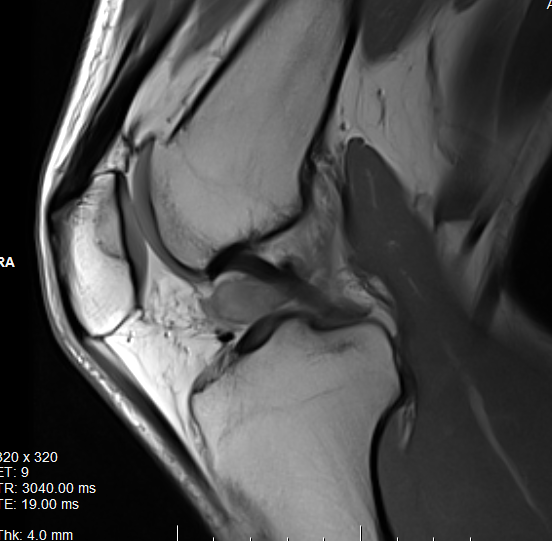

MRI

Synovial thickening

Hemosiderin

- low signal intensity on TI and T2 - "drop out" signals

- blooming on gradient echo

Localized posterolateral PVNS

Diffuse

Diffuse PVNS with involvement of suprapatella pouch and posterior compartments, including posterior extra-articular

Severe diffuse PVNS with bony involvement